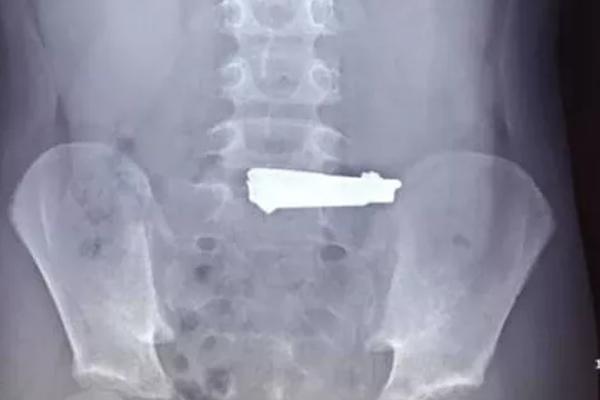

Theo bài chia sẻ, vào một buổi lên lớp, chị M. phát hiện một vài học sinh trong lớp ở tay có nhiều vết giống dùng dao rạch ở tay, có em rạch từ 21 đến 27 nhát.

Ngay lập tức, chị M. nhắn tin cho các phụ huynh, cảnh báo tình trạng nhiều em học sinh học theo các video thử thách trên youtube, làm "những việc rùng mình". "Các em mang dao lam đi và rạch vào tay mình các chữ như hận đàn ông, hận đời hoặc tên mình", cô M. viết.

Các em mang theo dao lam và rạch vào tay mình.